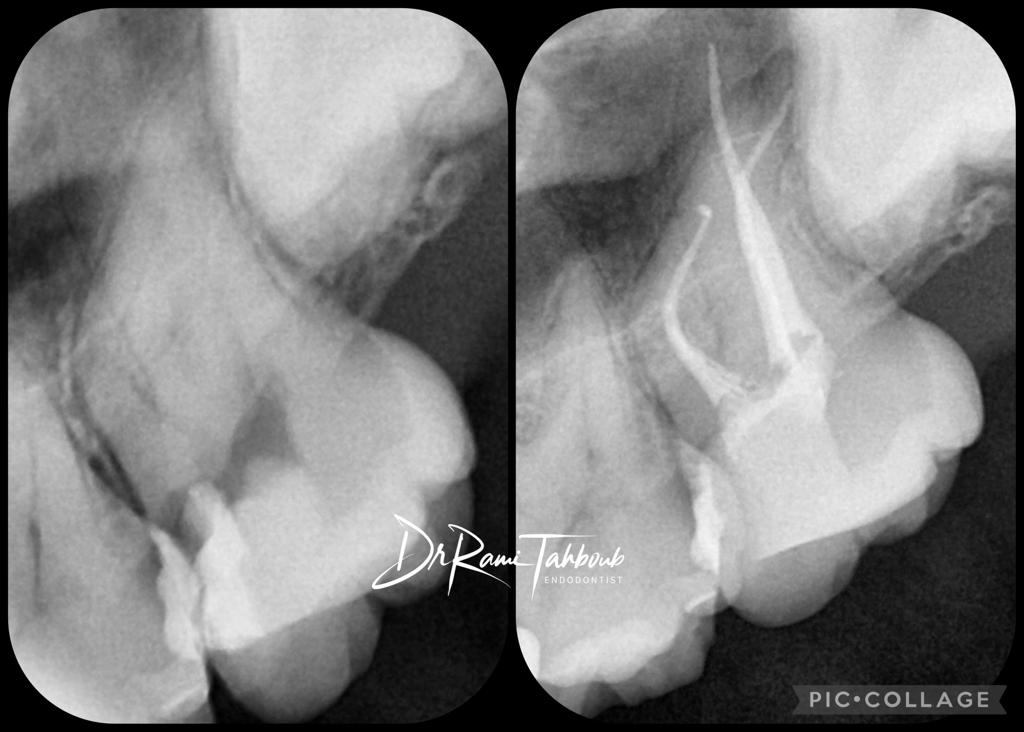

Your endodontist will start with medical & dental history taking. A radiograph (X-ray) will be taken to the tooth/teeth in question to help

& diagnosis & treatment plan.